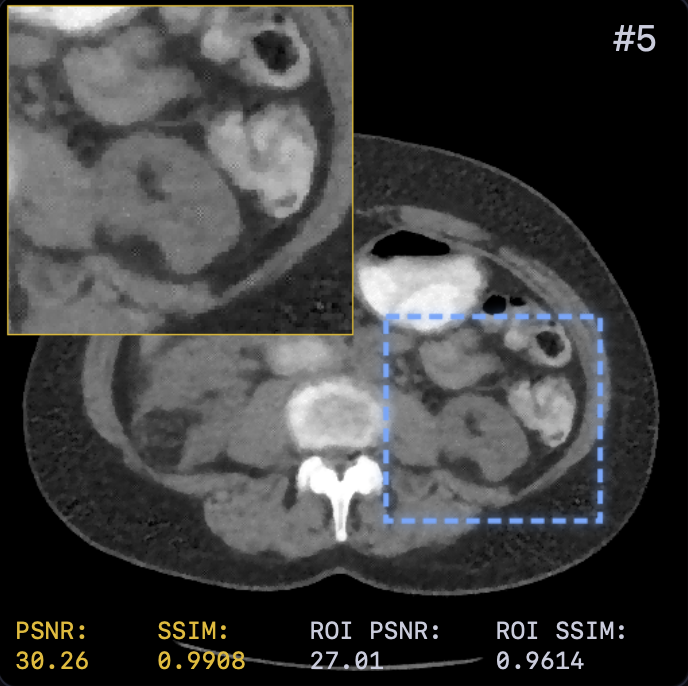

Table I presents the quantitative comparison. LTV achieves the best overall performance, surpassing FBP+U-Net [5] by approximately dB PSNR. Notably, learning the solver dynamics yields a consistent gain ( dB PSNR) over the fixed-solver baseline (29.42 vs. 30.15 dB). This confirms that end-to-end optimization of step sizes and relaxation provides modeling capacity beyond spatial adaptivity alone.

Qualitative results (Fig. 2) demonstrate that LTV preserves fine structures (e.g., vessel continuity) while avoiding the over-smoothing of classical TV and the anatomical inconsistencies of FBP+U-Net. This is corroborated by the error maps in Fig. 3, where LTV exhibits smaller and more spatially uniform residuals, indicating a balanced trade-off between noise suppression and detail preservation.